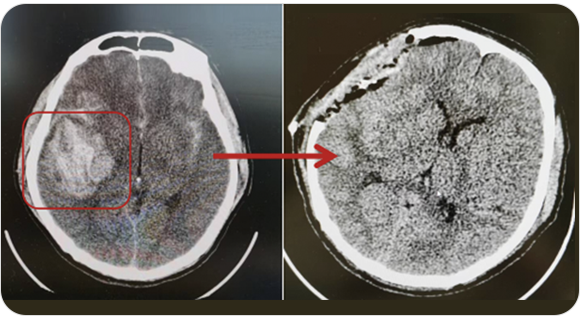

從事神經(jīng)外科工作30年,擅長腦與脊髓血管類疾病、腫瘤、外傷等疾病的診斷與治療,尤其擅長神經(jīng)介入治療各類腦血管疾病。累計完成介入栓塞顱內(nèi)動脈瘤2000多例,顱內(nèi)血管畸形數(shù)百例,夾閉顱內(nèi)動脈瘤數(shù)百例,手術(shù)顱內(nèi)與脊髓腫瘤數(shù)百例。在腦和脊髓血管病、腫瘤、外傷等方面有豐富的經(jīng)驗和較深造詣。

精通顱內(nèi)動脈瘤介入栓塞和手術(shù)夾閉雙技術(shù),系統(tǒng)掌握腦動靜脈畸形、頸內(nèi)動脈海綿竇漏、硬腦膜動靜脈漏等顱內(nèi)血管疾病的診療和手術(shù),精通頸動脈、椎動脈狹窄的血管內(nèi)重建技術(shù),以及頸動脈狹窄的內(nèi)膜剝脫手術(shù)技術(shù)。在顱內(nèi)腫瘤、椎管內(nèi)腫瘤、顱腦損傷、高血壓腦出血等疾病的診治和手術(shù),腦功能性疾病立體定向手術(shù)治療等方面也積累了豐富的經(jīng)驗。